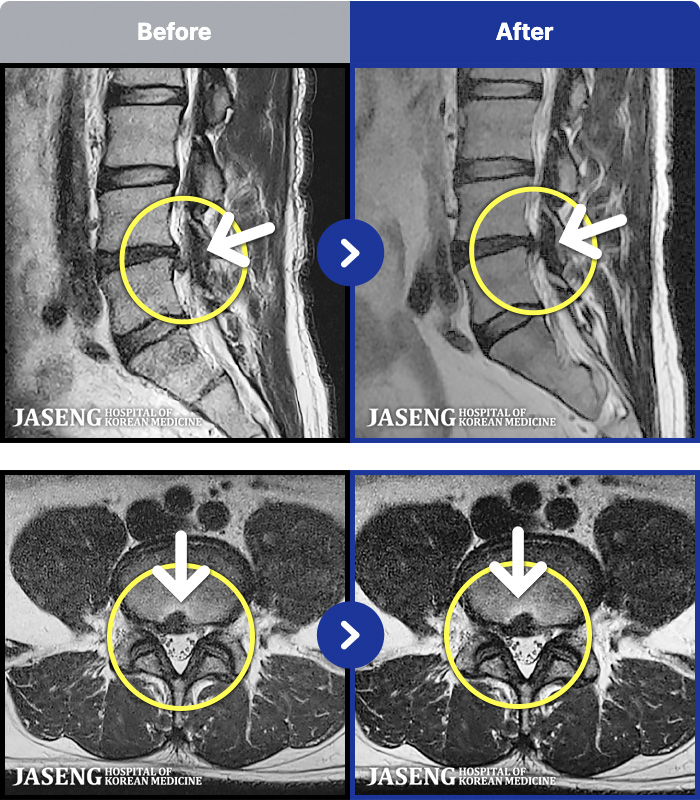

MRI ġ

1,299 MRI ũ ʸ Ȯϼ.